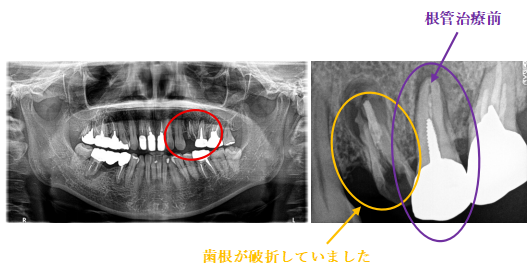

女性Sさん 50代(オールセラミック冠)

主訴

左上の差し歯がとれたままになっている。

治療内容

レントゲンを撮り詳しく診てみると、歯根が破折して保存することができず、抜歯する必要があることがわかりました。抜歯後、オールセラミックブリッジで補綴(欠損した部分を人工物で補う)しました。ブリッジの支台になっている後方の歯は、根尖性歯周炎(根の先端で問題を起こしている)でしたので、根管治療をしています。

所感

抜歯後、欠損部分を補う方法には、1本だけの部分入れ歯、ブリッジ、インプラントの3つの方法があります。この患者さんは、ブリッジを選択されました。メタルフリーの治療を希望されましたので、土台をファイバーコアにし、オールセラミックのブリッジをかぶせました。患者さんは、お口の中の金属を徐々に減らしていきたいということです。体全体の健康のことを考えると正しいことです。

オールセラミック冠(失活歯)1本:¥104,500(税込)

オールセラミック冠(生活歯)1本:¥93,500(税込)

ポンティック1本:¥93,500(税込)

合計:¥291,500(税込)